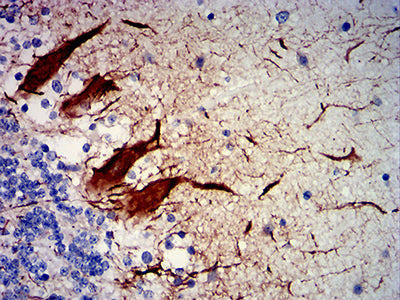

分类: 科研抗体货号: 31909别名: NFH; CMT2CC应用: IHC,FCM反应种属: Human

-

分类: 科研抗体货号: 31908别名: NFH; CMT2CC应用: IHC反应种属: Human

-